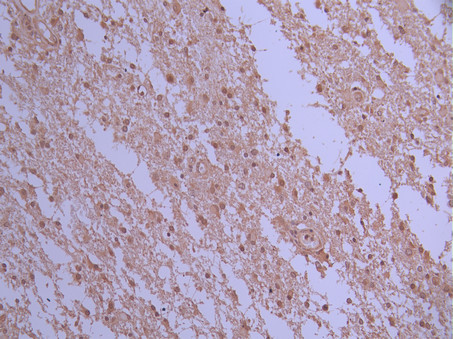

• IHC image of CSB-RA599252A0HU diluted at 1:100 and staining in paraffin-embedded human glioma cancer performed on a Leica BondTM system. After dewaxing and hydration, antigen retrieval was mediated by high pressure in a citrate buffer (pH 6.0). Section was blocked with 10% normal goat serum 30min at RT. Then primary antibody (1% BSA) was incubated at 4°C overnight. The primary is detected by a Goat anti-rabbit polymer IgG labeled by HRP and visualized using 0.05% DAB.